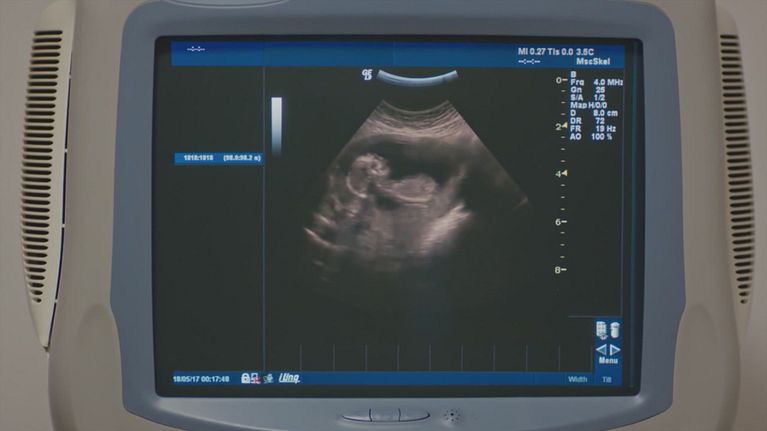

La prima ecografia

Cesur accompagna Suhan alla prima ecografia e per la prima volta vedono insieme il loro bambino.